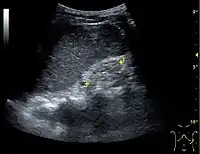

Ultrasound

Kidney ultrasonography is useful for diagnostic and prognostic purposes in chronic kidney disease. Whether the underlying pathologic change is glomerular sclerosis, tubular atrophy, interstitial fibrosis, or inflammation, the result is often increased echogenicity of the cortex. The echogenicity of the kidney should be related to the echogenicity of either the liver or the spleen (Figure 22 and Figure 23). Moreover, decreased kidney size and cortical thinning are also often seen and especially when disease progresses (Figure 24 and Figure 25). However, kidney size correlates to height, and short persons tend to have small kidneys; thus, kidney size as the only parameter is not reliable.[54]